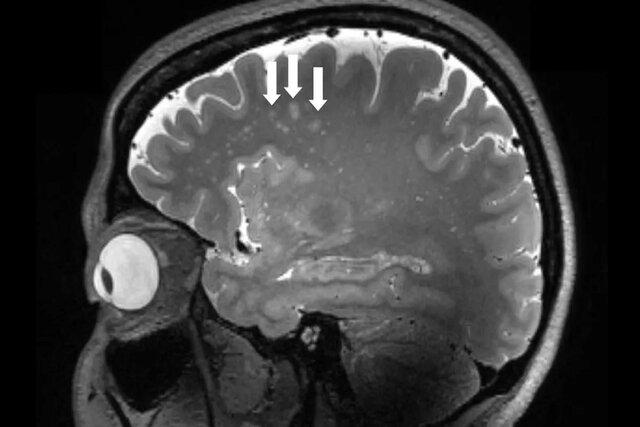

تصاویری که تاکنون مشاهده نشده بود، نشان میدهد که میگرن در مغز چگونه است و این میتواند به پزشکان کمک کند تا راههای جدید و